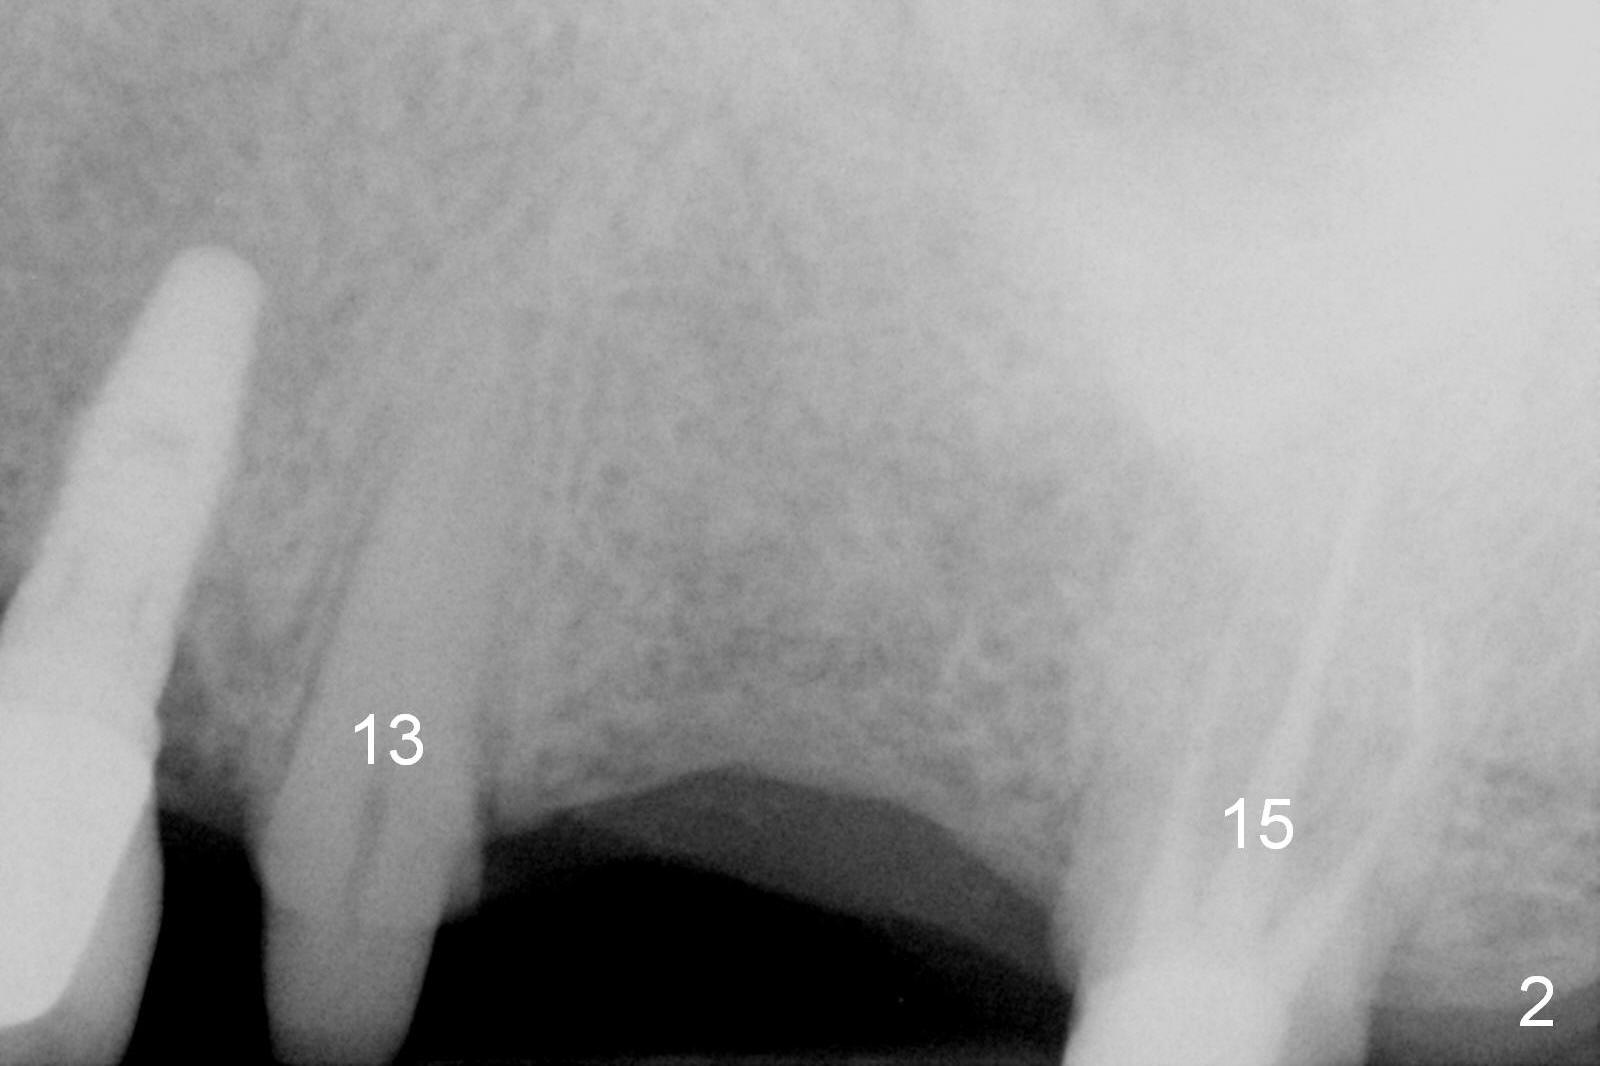

A 73-year-old man returned for recall and had panoramic X-ray taken yesterday. The latter shows no bone loss associated with different types of implants (Fig.1). The implants (relatively small in diameter) and crowns were present at the sites of #3 and 12 when the patient presented to my clinic 6 years ago. His chief complaint was discomfort at #13-15 fixed partial denture (FPD). The tooth #15 seems to be without pathology. To increase its longevity, the FPD was removed (Fig.2), a 5x8 mm Bicon implant (short) was placed at #14 (5 years 11 months post cementation now) and single unit restorations were cemented at #13 and 15 (Fig.3). The occlusal table of the implant crown at #14 is narrow buccopalatally (Fig.4). The occlusal contact of the implant restoration is minimal (Fig.5), which is unfavorable for the weakened tooth (#15). The latter shows sign of failure 7 months post #14 crown cementation (Fig.6 >). The patient refused to accept treatment for #15. Seven months later, the tooth #5 fractured (1st sign of bruxism) and a 5x20 mm cylindrical Tatum tissue-level implant (long) was placed immediately (4 years 5 months in function now). Finally the patient agrees with immediate implant at #15 (7x17 mm tapered Tatum tissue-level implant, large). Follow up is 2 years 7 months post cementation. Ideally 2 implants should have been placed when the FPD was removed. To reduce deleterious effect of bruxism, the last implant was placed with bone expansion at the edentulous area at #2 (5.3x14 mm DIO submerged implant, 1 year 9 months post cementation now). The 2nd sign of bruxism is placement of inlay/onlay on the teeth #19 and 30 (Fig.1). The palatal cusp of the implant crown at #13 remains untreated. The 2 immediate implants at #5 and 15 happen not to have immediate provisional. In all, for a bruxer, an implant does not have to be large or long as long as implant trajectory is correct.